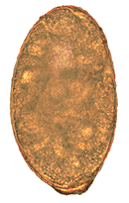

An egg of Nanophyetus salmincola

Eggs of N. salmincola are light brown, ovoid, and operculate at one end, with a small blunt projection at the other end. They measure 0.087 mm to 0.097 mm by 0.038 mm to 0.055 mm.[12] There are normally 5 to 16 eggs in the uterus, and their heaviness allows them to sink rapidly in water.[12]